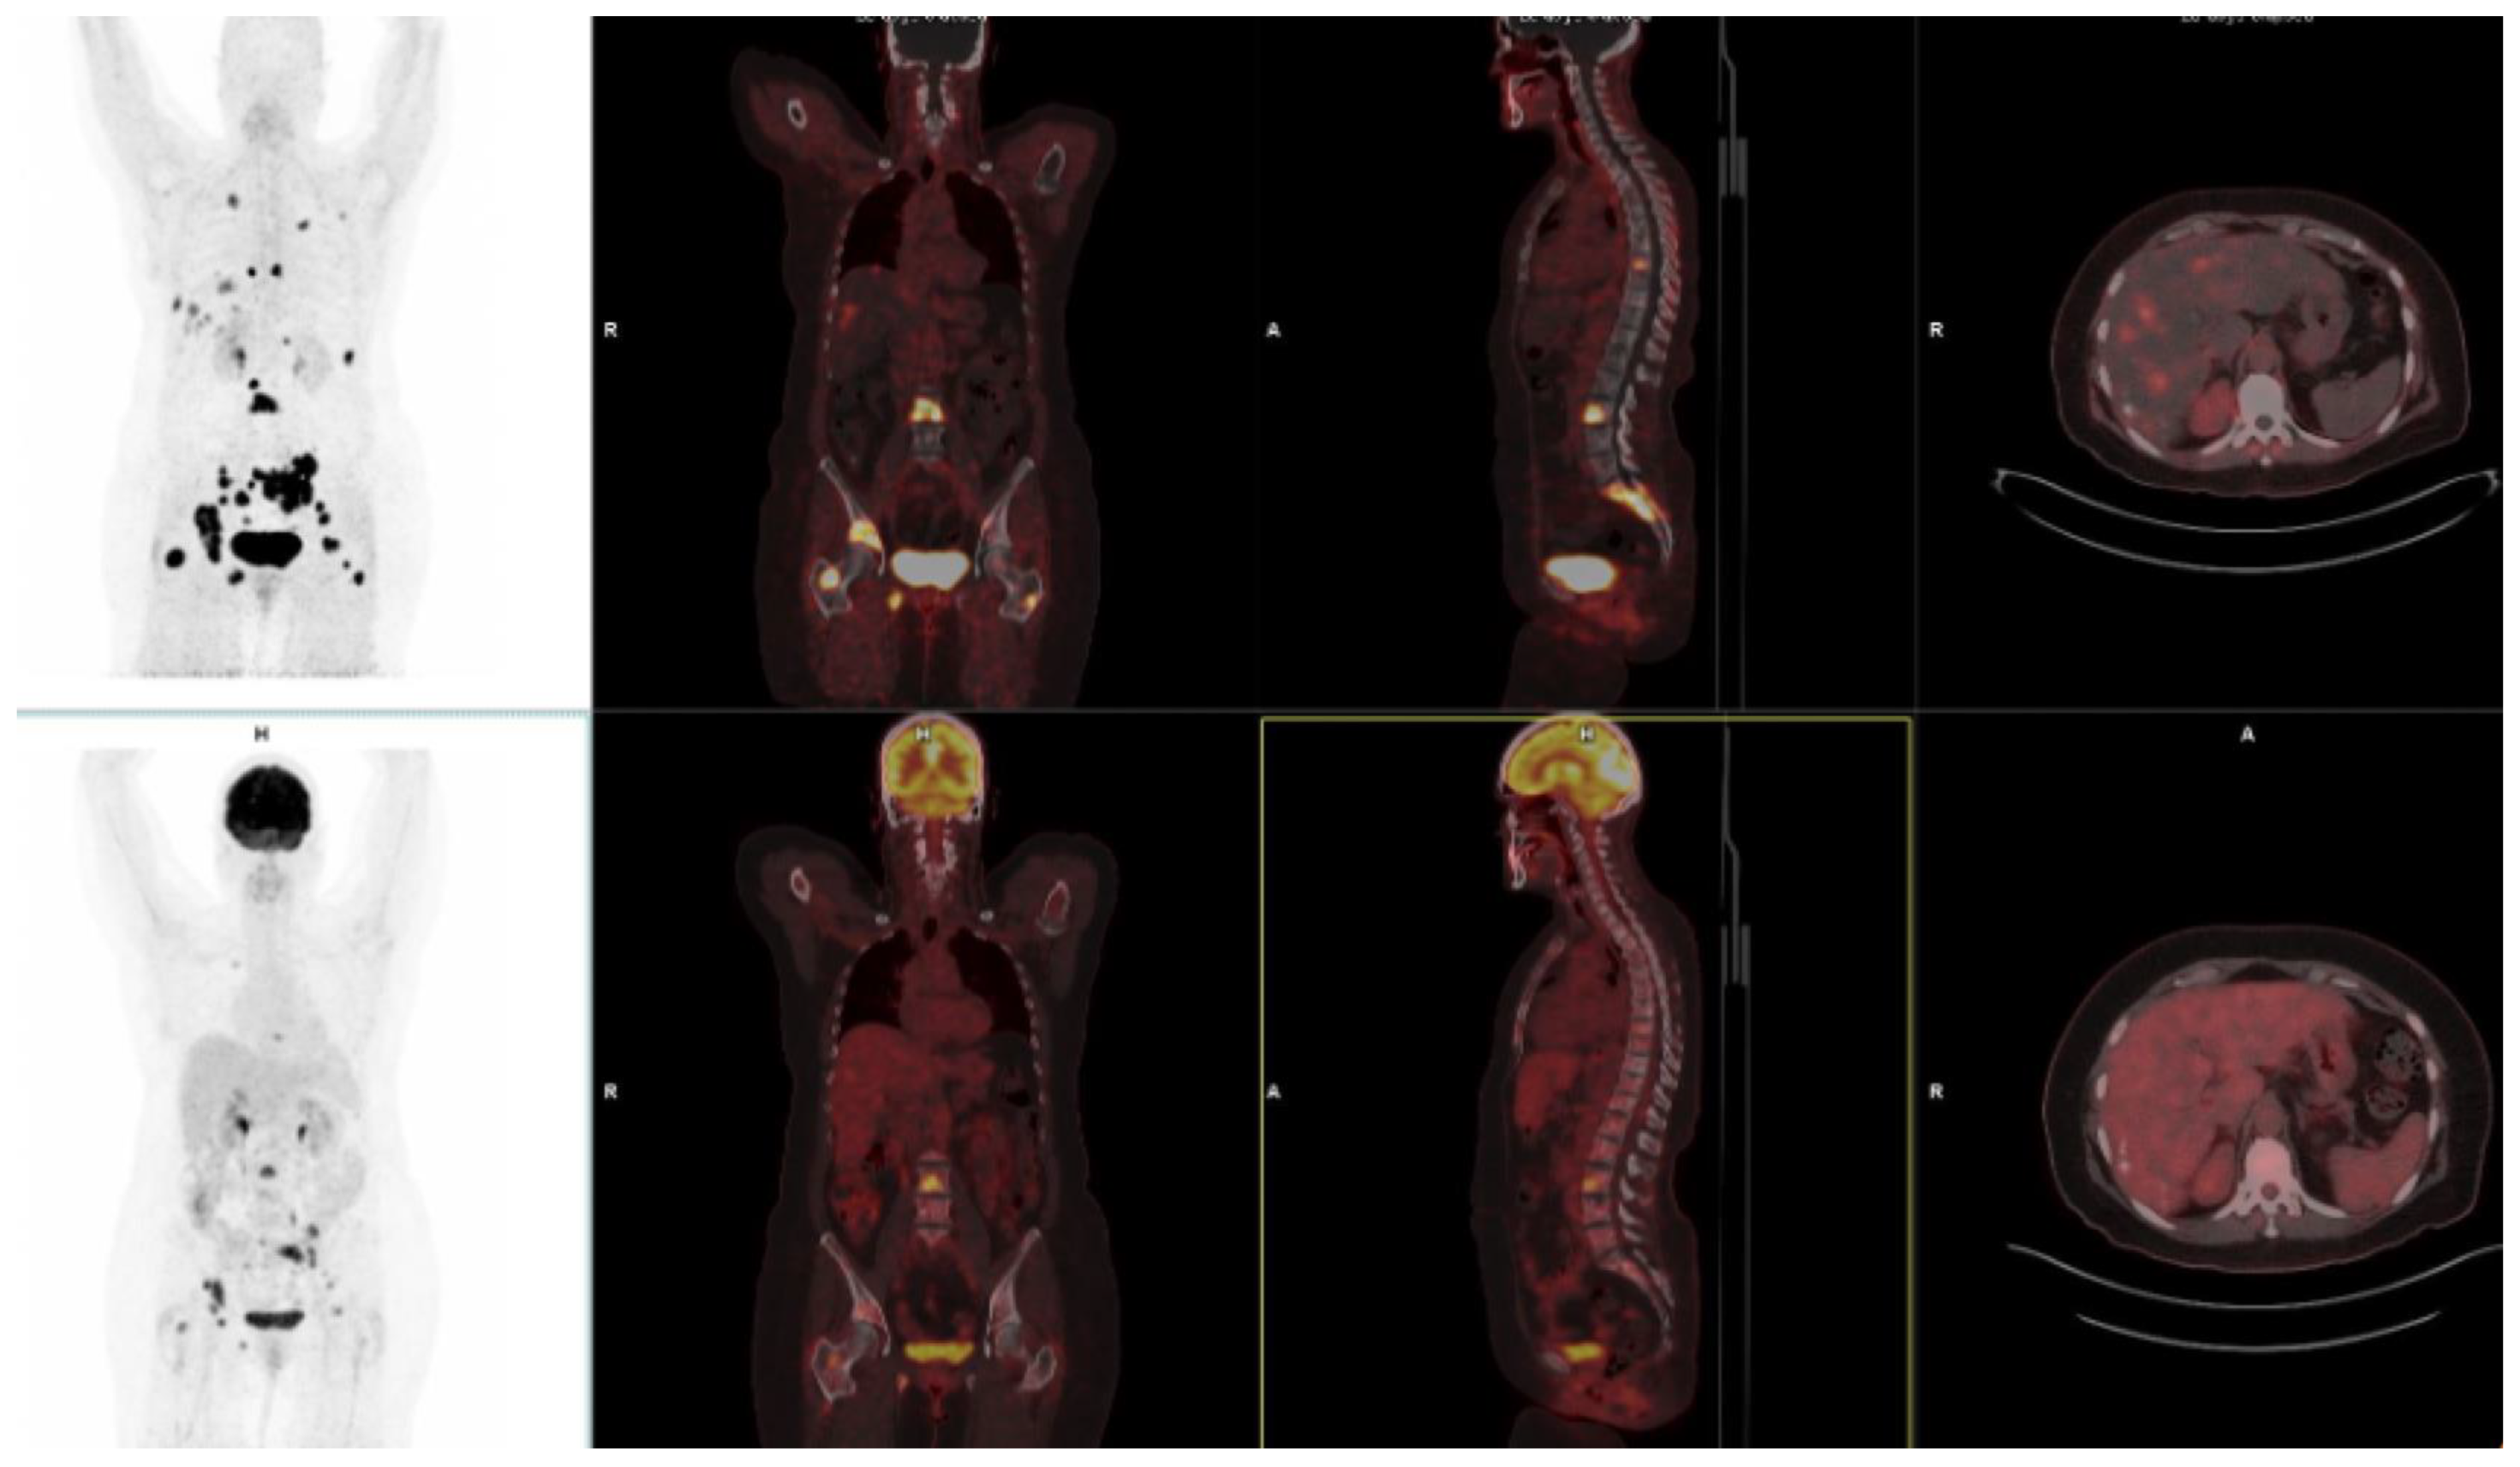

FAPI-Based Radioligands

3.10. Pancreatic Cancer

3.11. Hepatocellular Carcinoma

10. FAPI-Based Theranostic Approaches

12. The Potential Role of FAPI PET-Based Theranostic Approaches